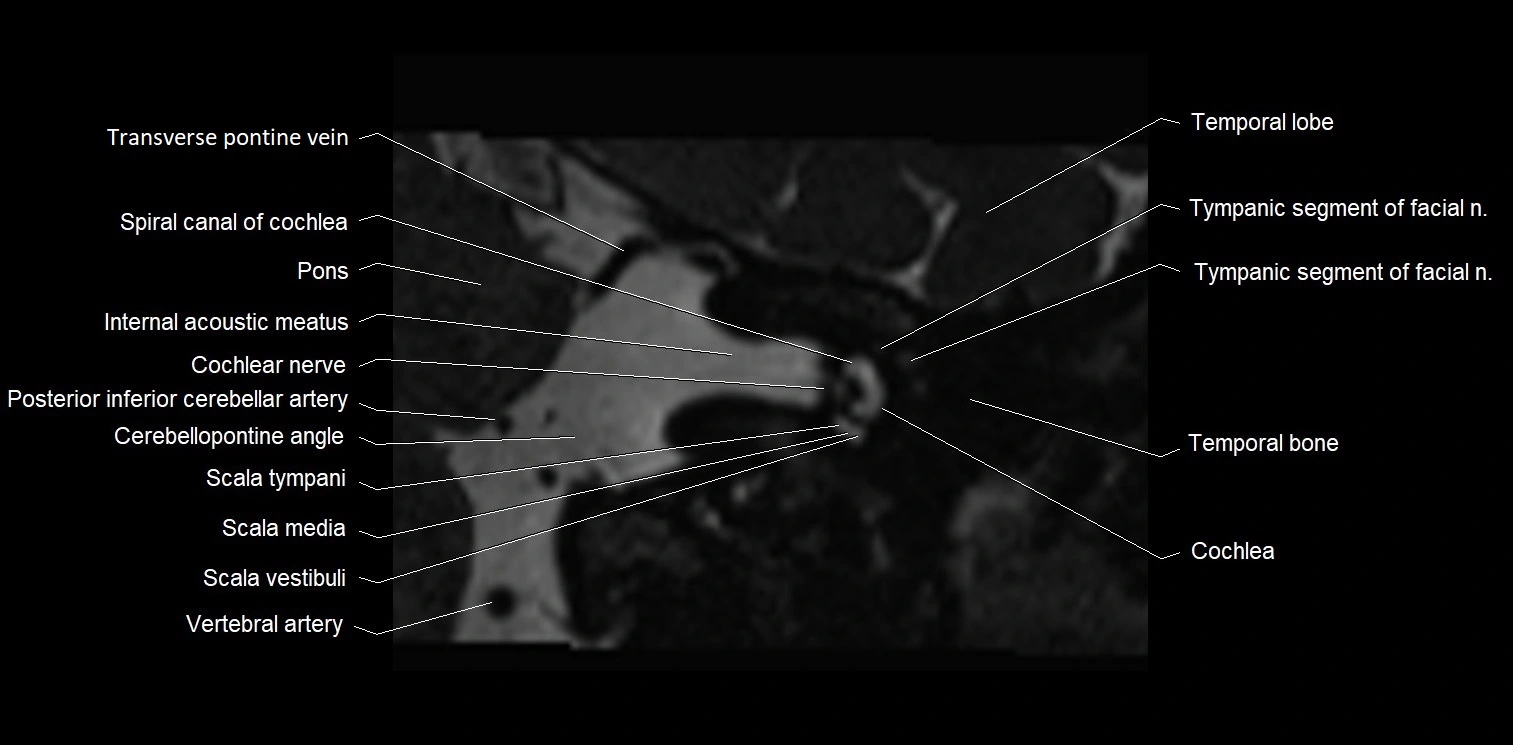

MRI images

image